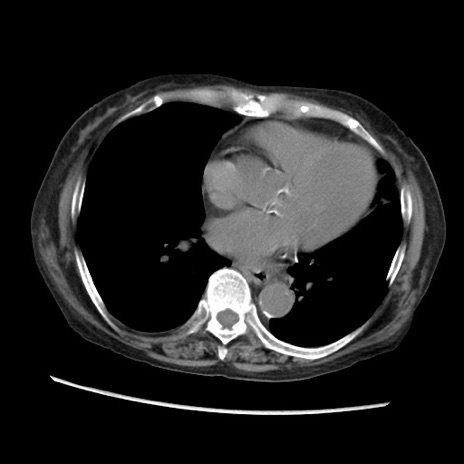

冠状断像